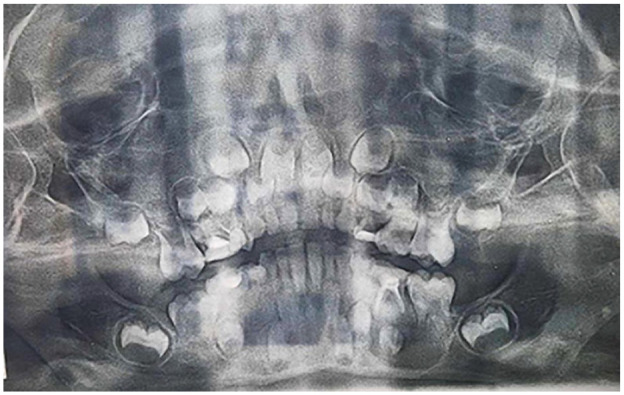

Dentigerous cysts are the most common type of developmental odontogenic cysts. Multiple devices has been described for decompression. The current case report describes the use of a custom-made decompression appliance, designed through a digital workflow, in managing dentigerous cysts. A 7-year-old male patient with no prior medical history was referred to our oral surgery department due to swelling on the left side of the lower jaw. Upon intraoral examination and cone-beam computed tomography (CBCT), a provisional diagnosis of an inflammatory dentigerous cyst related to the impacted premolar was made. A digital decompression appliance was planned using EXOCAD (Exocad Gmbh, Darmstadt, Germany), and produced using a stereolithography (SLA) 3D printer. The appliance were delivered on the day of the cystostomy after extraction of the deciduous molar (tooth 85). In this report, the advancements in digital design technologies were explored enabling the creation of customized cyst decompression devices. Various stages of the design process were discussed, including 3D modeling, material selection, and the integration of digital workflows in the fabrication process. Additionally, the benefits of using such devices were addressed, including improved patient outcomes, enhanced precision in treatment, and the reduction of surgical complications.